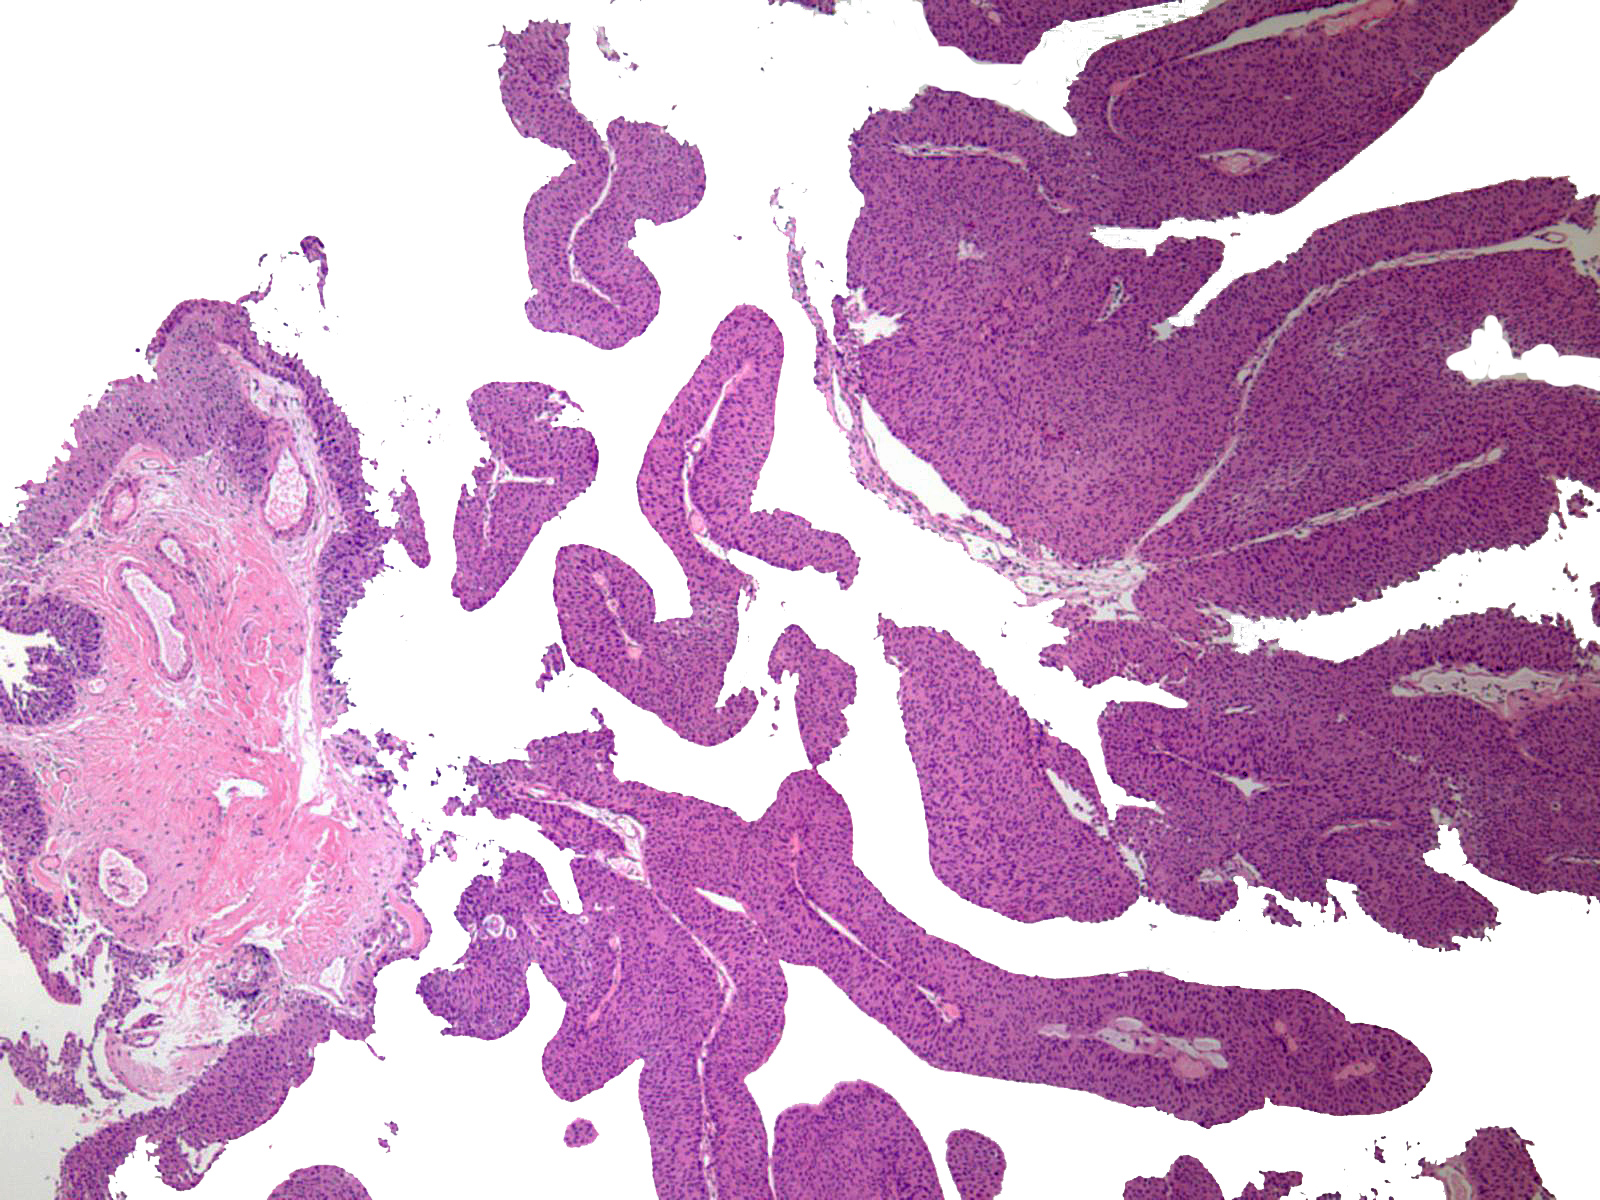

Consensus grade: Low-grade papillary urothelial carcinoma (LG-PUC)

Lesion shows moderate variation in nuclear size, shape and chromatin. Scattered nuclei are significantly enlarged and hyperchromatic relative to other nuclei. Lesion still maintains an overall orderly appearance.